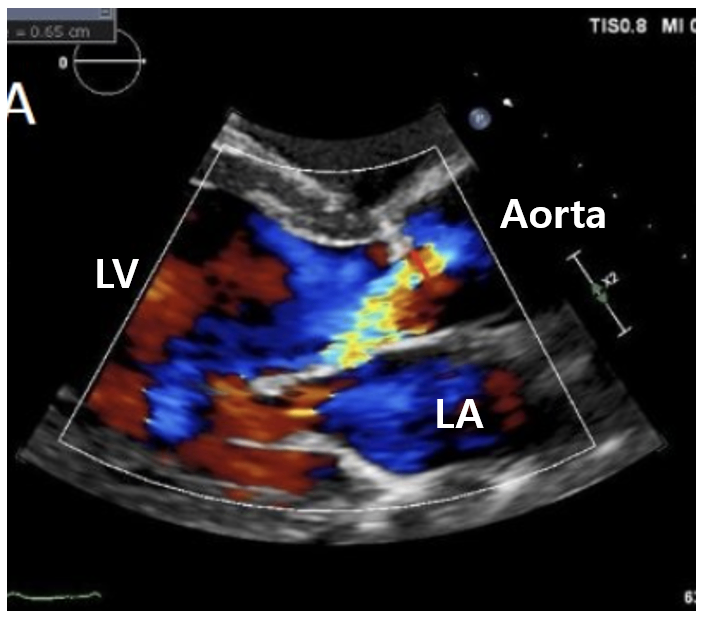

1) 경흉부심초음파(transthoracic echocardiography, TTE): 1st line

(1) Doppler 초음파 상 역류 확인

① Probe에 가까워지는 혈류는 붉은색, 멀어지는 혈류는 푸른색

② Turbulent flow가 있으면 붉은색/노란색/푸른색이 불규칙하게 섞여있는 패턴 발생 → 역류 시사

(2) LV의 eccentric hypertrophy

(3) 기타: AR 크기/역류량, AV 형태, LA/LV 크기, LV/RV 기능, 폐동맥압 등